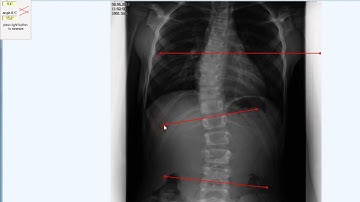

20 Multiple Cobb Angles Tool